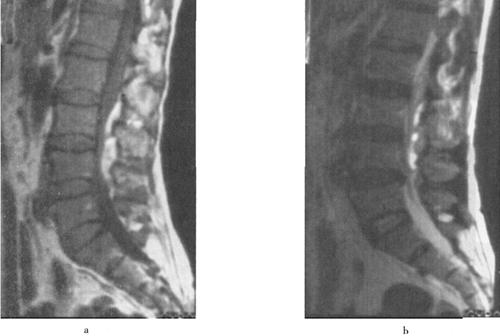

图7-15 颈髓挫裂伤:T1W(a)T2W(b)矢状面,脊髓增粒为髓水肿所致,T1W和T2W信号增高。横断面(c)脊髓内可见斑片状出血灶,硬膜外血肿T2W亦呈高信号,脊髓压迫向右后移位。颈后方软组织出血水肿,在T2W亦为高信号